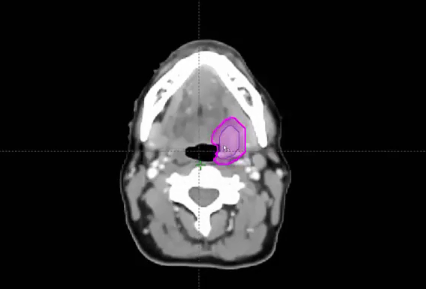

nasopharynx, MRI, PET, CT, NPX carcinoma, balloon procedure, right nasal pharyngeal carcinoma, 2A node, microscopic disease, T1, CLL, right parotid mass, squamous cell, right superficial parotidectomy, modified neck dissection, right temporal skin lesion excision, lymph node, ECE, bolus, dissecte...